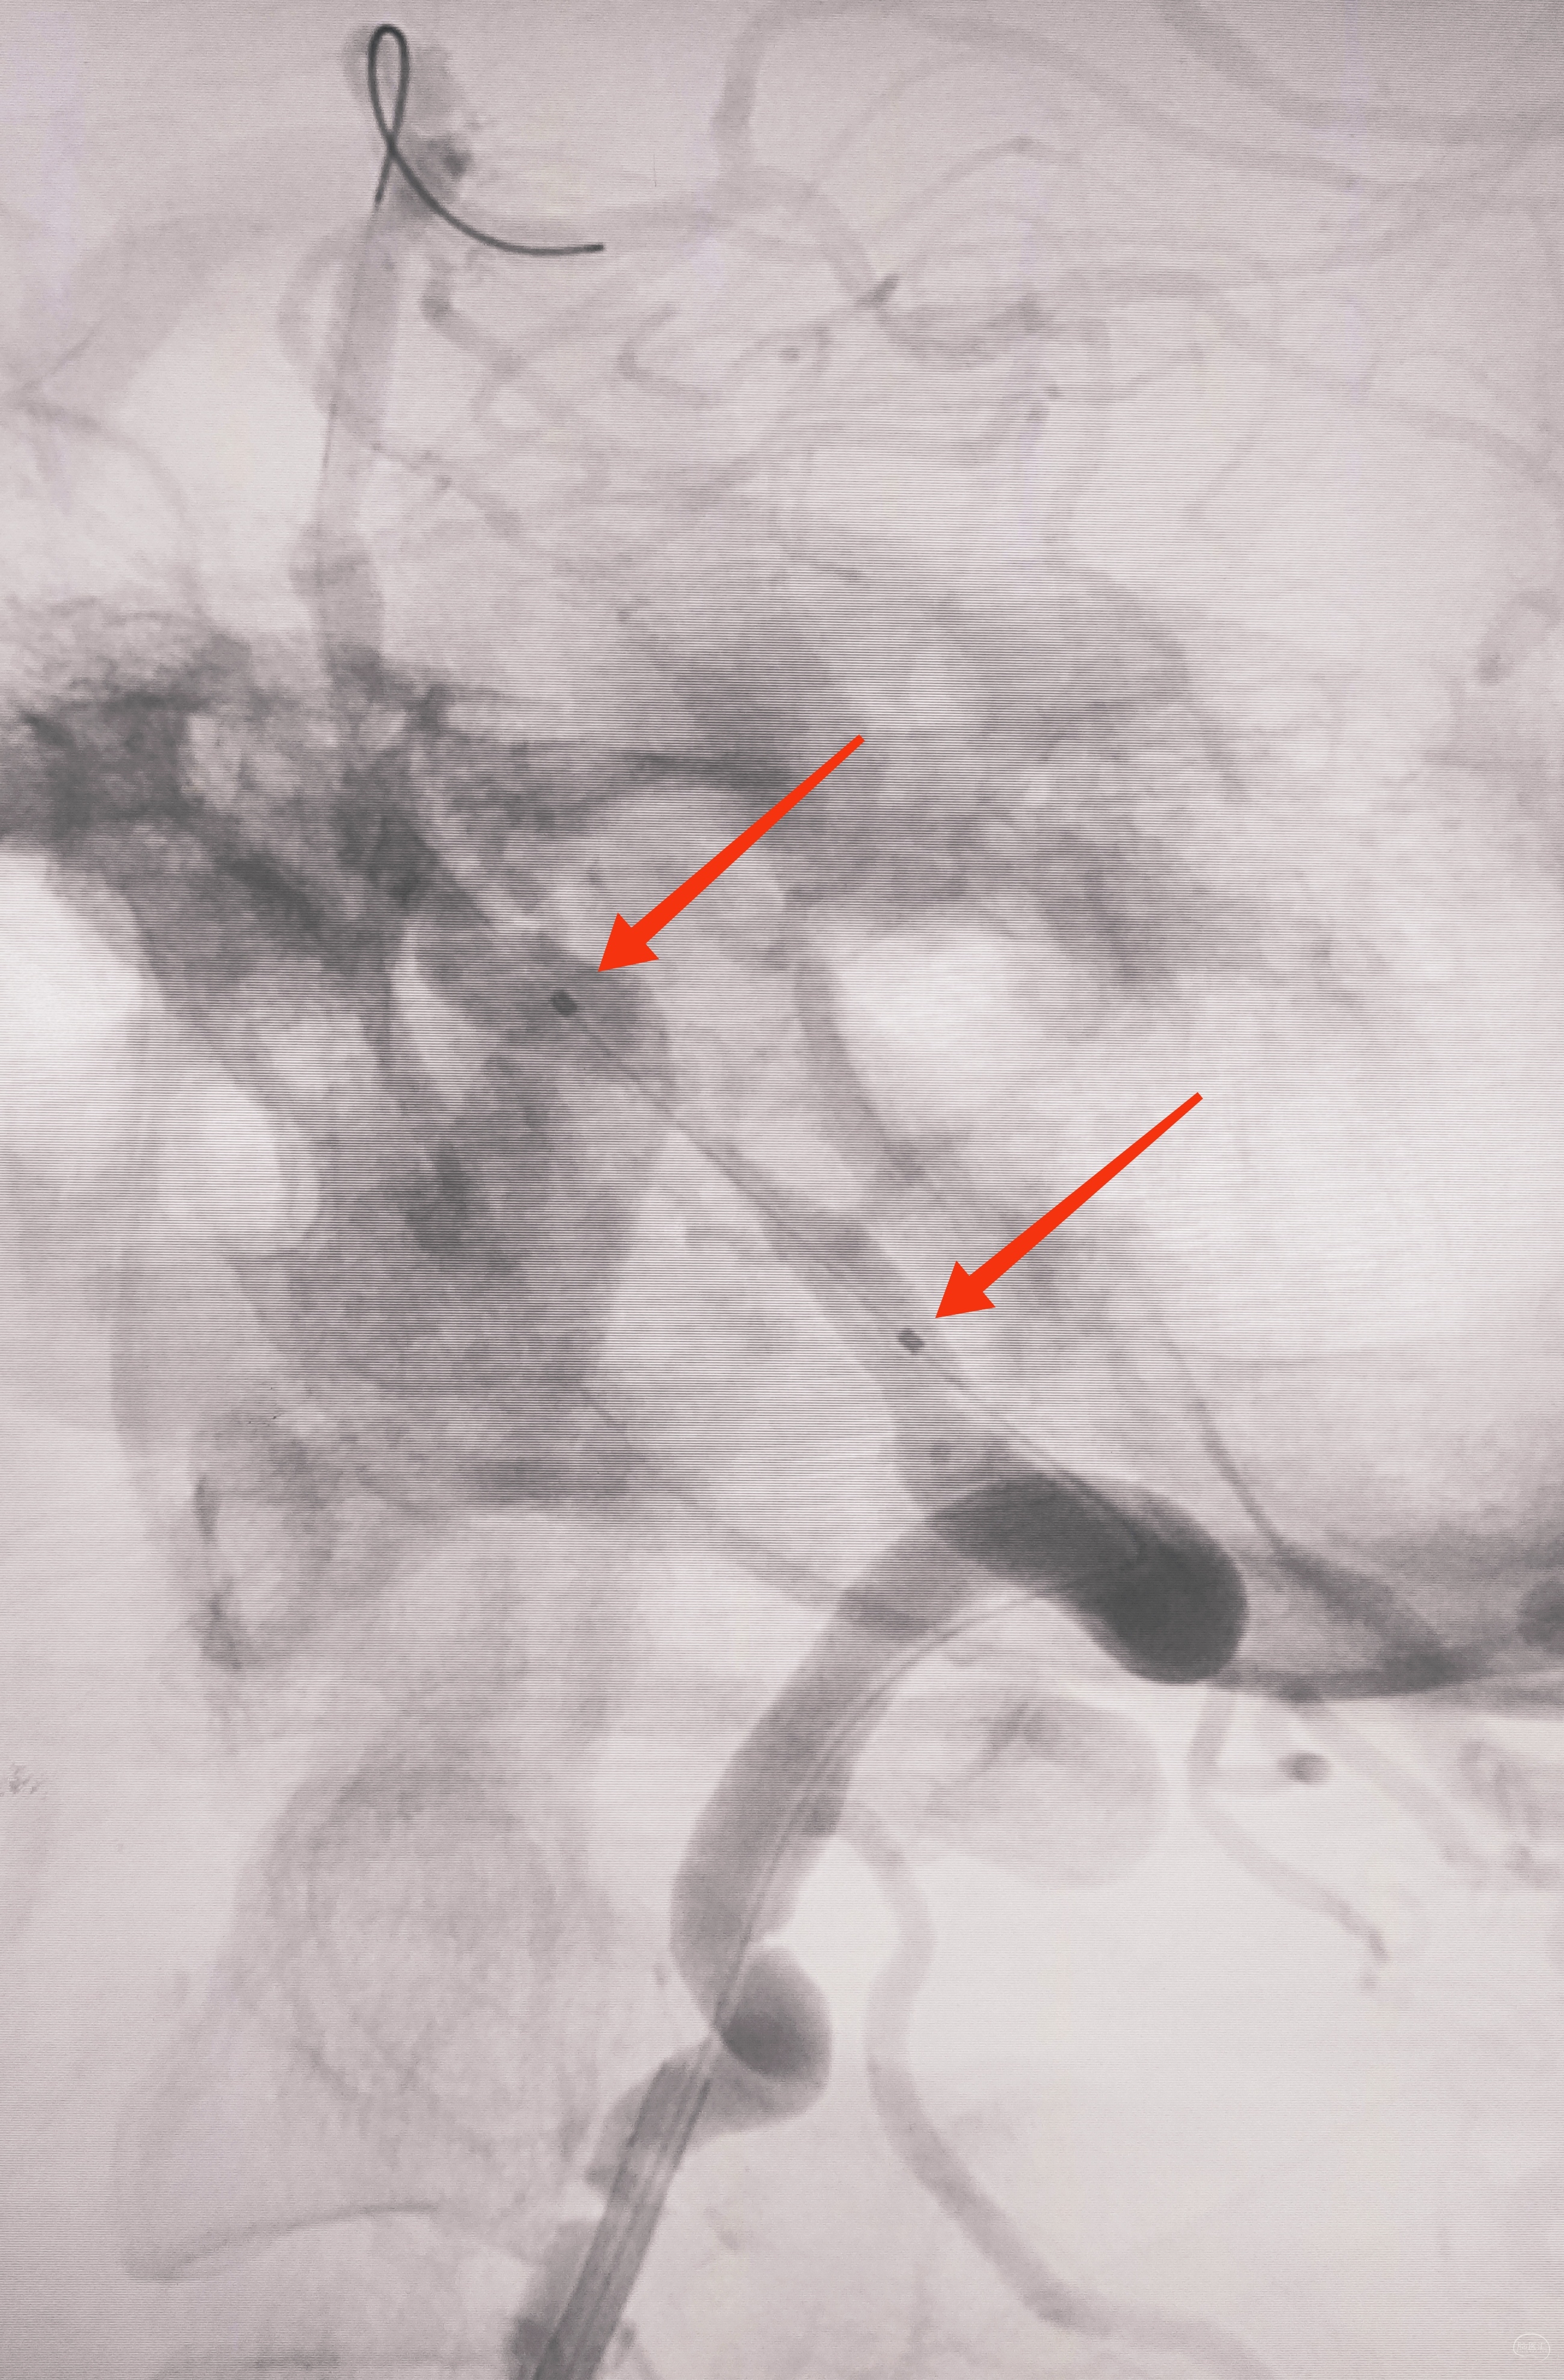

因为是极重度狭窄,支架前拟小球囊预扩,谨慎起见,置入泰杰Proender保护伞并打开,以免不测

梯度预扩,先雅培1.5×15小球囊预扩

再Sino3×20球囊预扩

预扩满意,保护伞不浪费,借助保护伞的支撑和保护作用,上送导引导管(不怕掉斑块,物尽其用),为颅内狭窄处理提供更佳支撑

看图说话,没啥聊的。球囊不浪费,Sino3×20球囊预扩V4狭窄

EP4.5×22支架置入

导引导管保持原位,导管内安全输送Herculink5×20,通过椎开口狭窄并走远,再回撤导引导管至锁骨下动脉

球扩支架顺利释放